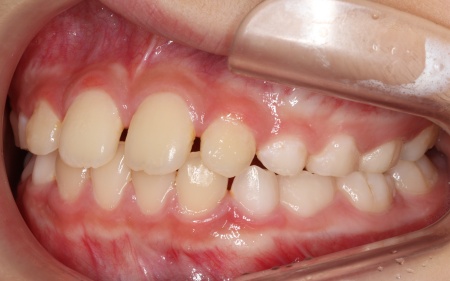

治療後

お子様の成長に合わせて慎重に治療を進めることで、無理のない自然な形で歯並びと噛み合わせを改善することができました。